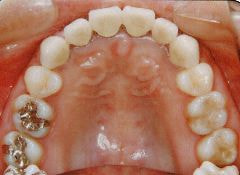

治療例2 (補綴処置+矯正)